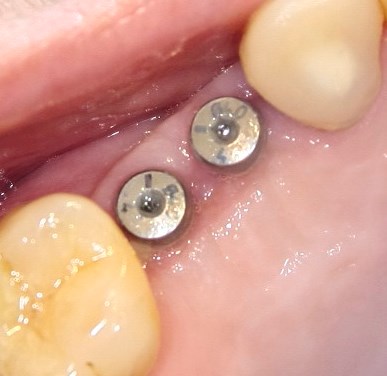

Опыт применения коллагеновой матрицы Mucograft в клинической практике.